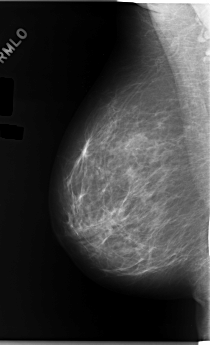

C_0170_1.LEFT_MLO

LEFT_MLO LINES 5952 PIXELS_PER_LINE 3264 BITS_PER_PIXEL 12 RESOLUTION 50 OVERLAY